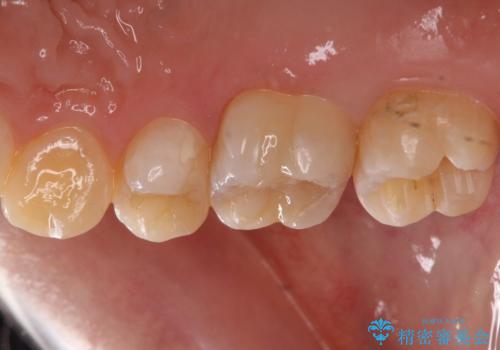

銀歯を白くしたい

- 奥歯の銀の詰め物を白くしたいとのことで来院されました。

- 右上7 セラミックインレー 77,000円費用は治療当時の料金となります

今回は大きな虫歯もなかったため、1回当たり30分程度の治療時間で計2回の来院回数で治療を終えることができました。